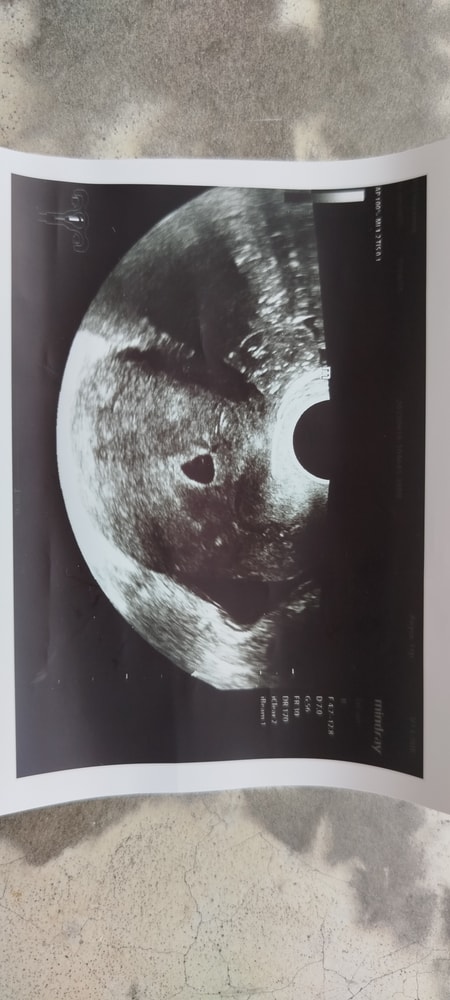

На 23 дпп УЗИ свд 11.5, желточный мешочек 3.3.

26дпп свд 10.8 желточного мешка не видно узист другой

На 23 дпп УЗИ свд 11.5, желточный мешочек 3.3.

26дпп свд 10.8 желточного мешка не видно узист другой

Вон же там кружочек, это же мешочек? И яркое пятнышко, это где должен появиться эмбрион?